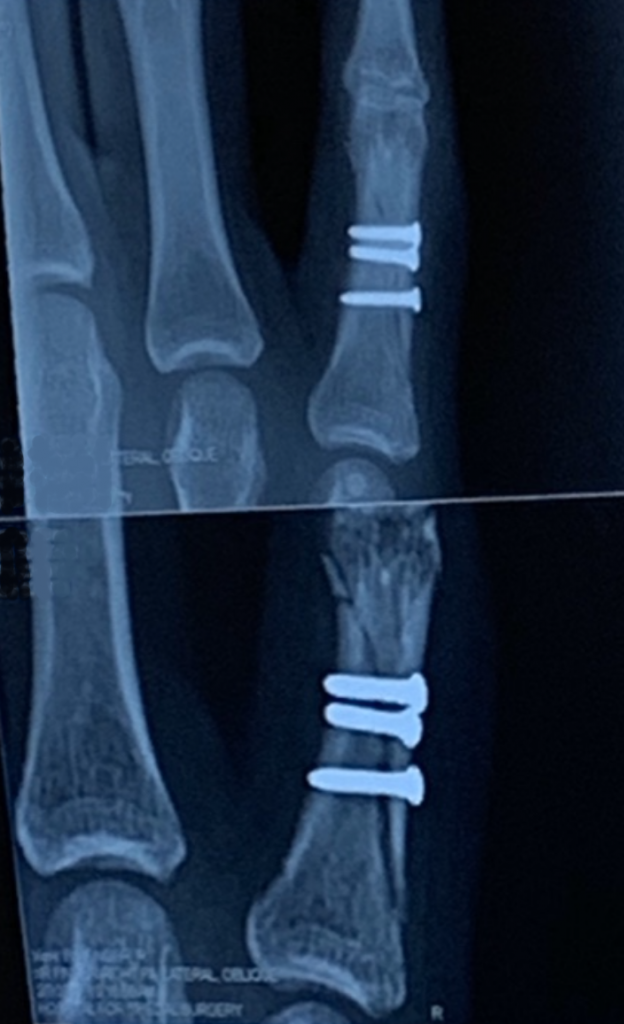

I suffered a complex dislocation of my left pinky finger on the basketball court and was transported via ambulance to the Cornell-Presbyterian hospital, where I felt largely ignored and had to make the proactive effort to get a doctor to my room on two occasions during a six-hour ER visit. The doctors seemed courteous and competent, just not very attentive ... even though there didn't seem to be many patients needing care at the time. To make matters worse, I was given Cornell-related numbers for follow-up care and possible surgery. To my consternation, I was told that the soonest they could get me in for an appointment was 6 to 7 weeks away ... huh?!!

The reason I provide this horrific context is because, once I expressed my extreme displeasure, I was referred to doctors at the the Hospital for Special Surgery (HSS) and scheduled an appointment with Dr. Steve Lee ... where my experience was completely different (in an extremely positive way). I contacted his office staff who let me know that he had not planned to be in that afternoon, but - based on my description of the injury and the fact that I am a musician whose hands/fingers are crucially important to my well-being - he felt that I needed to be seen right away, so asked that I be put on the books for that very afternoon. After carefully examining my injury, Dr. Lee scheduled me for surgery the next morning. In contrast to my assessment of the Cornell ER experience (very negative), I felt that this examination experience and scheduling process were the most positive ever; it was clearly evident that this doctor and his staff were interested in caring for me in the manner that would best serve my needs and were willing to make every effort to ensure that is precisely what happened!

In fact, during the surgery, Dr. Lee found numerous pieces of "debris" and a piece of gravel in my stitched finger ... as a result, waiting the 6 to 7 weeks Cornell offered would have been very dangerous to my health and could have resulted in significant infection or other complications. Though I would not wish the injury I experienced on my worst enemy, should such an injury occur to anyone I know, I will STRONGLY recommend the HSS services in general; and Dr. Lee specifically. It is now just over three weeks after the accident, and physical therapy (also at HSS) has improved the mobility of my finger substantially. I have no doubt that, within the coming weeks, I will recover most of the injured finger's dexterity ... and, with continuing work, will eventually recover fully. This is largely due to the care and timely help of Dr. Lee and HSS. Thank you for ALL that you have done for me!! Simply put, I cannot rate your services high enough!